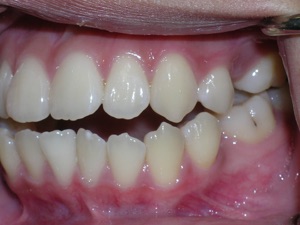

So here’s a case of an open bite, with a protrusion. There was a fair degree of crowding as well.

Here are the results.